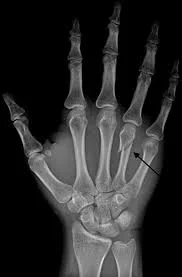

• Acute and chronic hand injuries, including soft tissue injuries and bone and joint injuries

• All hand fractures and broken bones, including finger fractures, carpal bone fractures and scaphoid fractures